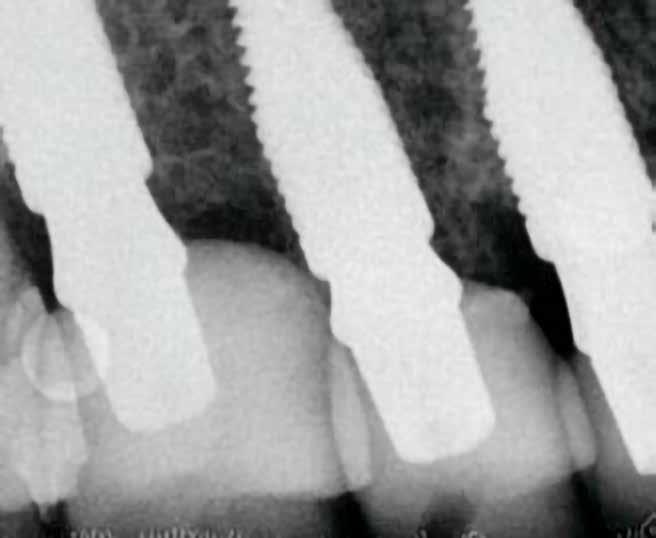

A végleges ragasztást követően röntgenfelvételt készítettünk, amelyet összevetettünk a közvetlenül a műtét után készült felvételekkel: a marginális csontszint változatlan volt. A pácienseket 14 hónapon keresztül rendszeresen visszahívtuk. Klinikai és röntgenvizsgálattal sem tapasztaltunk komplikációt (12. a–b ábrák)

lantátum 4,3 mm átmérőjű és 13 mm hosszúságú volt. A behajtási nyomaték mind a négy esetben 35–40 Ncm tartományban volt, amely lehetővé tette az azonnali terhelést. Tizenkét hónap elteltével egyik implantátumnál sem tapasztaltunk csontfelszívódást, a kemény- és a lágyszövetek stabilitása kielégítő volt.

Tanulmányunk célja összesen négy, rágó területre beültetett kétrészes Zi ceramic implant® kerámiaimplantátum (Neodent) teljesítményének értékelése volt. A legalább tizenkét hónapos utánkövetés alatt egyetlen esetben sem tapasztaltunk technikai vagy biológiai szövődményt, amely bizonyítja az implantátum osszeointegrációjának klinikai és radiológiai sikerét, valamint a lágy- és keményszövetek volumenének stabilitását. Eredményeink összhangban vannak más, azonos implantátumokkal és hasonló utánkövetési periódussal készült tanulmányok tapasztalataival [8, 10]. Korábbi, állatokon végzett vizsgálatok kimutatták, hogy a cirkónium-dioxid implantátumok osszeointegrációja megbízható és biztonságos, még különböző terhelési viszonyok mellett is [11, 12]. Mint azt korábban említettük, jelen tanulmányban mind a négy implantátum sikeresen osszeointegrálódott a vizsgált tizenkét hónap alatt.

Medentika® ÉLETHOSSZIG TARTÓ GARANCIA

Korábbi tanulmányok kimutatták, hogy a cirkónium-dioxid felületek hajlama a biofilmképződésre kisebb, mint a titánfelületeké [13]. Jelen vizsgálatban gyulladásos folyamatoktól mentes és egészséges megjelenésű periimplantáris szöveteket lehetett megfigyelni (12. a–b ábra). Egy másik, a jelen tanulmányban alkalmazott implantátumrendszerrel végzett prospektív klinikai vizsgálat kimutatta, hogy legalább tizenkét hónapos utánkövetés mellett sem volt tapasztalható kóros elváltozás a periimplantáris lágyszövetekben [8]. Ugyanez a tanulmány, egy további prospektív klinikai vizsgálat, valamint saját eredményeink egybehangzóan azt mutatják, hogy a marginális csont szintje a megfigyelt idő alatt stabil volt [8, 10, 14]. Az itt bemutatott két páciens kerámiaimplantátumokat kapott a felső moláris régióba. Komplikációkat, mint például az implantátum vagy a felépítmény törése, nem tapasztaltunk. Ez a tény megerősíti más tanulmányok megállapításait is, amelyek szerint a kerámia fogászati implantátumok gyártására az ittriummal stabilizált cirkónium-dioxid (YTZP) a legalkalmasabb. Az YTZP esztétikai és biológiai előnyei mellett a korrózióval, kopással és rágóerőkkel szembeni nagyfokú ellenálló képessége is kimagasló [15]. Érdemes megemlíteni, hogy jelen tanulmány tizenkét hónapos követési időszakot ölel fel, amely rövidnek számít. Azonban ezen időszak alatt nem tapasztaltunk klinikai vagy biológiai szövődményt, külö-

10. a ábra: Végleges lítium-diszilikát koronák. – 10. b ábra: Végleges monolitikus cirkónium-dioxid korona. – 11. a–b ábrák: Klinikai megjelenés tizenkét hónap elteltével. 12. a–b ábrák: Tizenkét hónapos kontrollröntgen-felvételek.